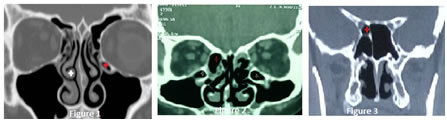

Figure 1                                           Figure 2                                   Figure 3

Figure 1: Bilateral paradoxical middle turbinate (white star) and Left Haller cell (red star); Figure 2: Bilateral Haller cells (white star) and Right side Prominent Bulla Ethmoidalis (Red star); Figure 3: Right side Onodi cell; Figure 4: Bilateral Maxillary Hypoplasia; Figure 5: Right Sphenoid aplasia; Figure 6: Left Uncinate process pneumatisation